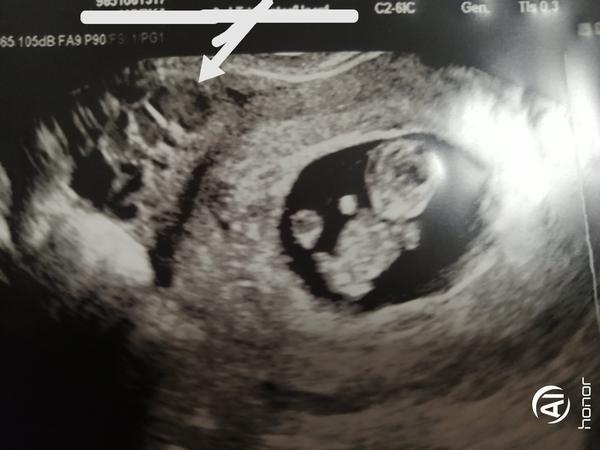

dnes jsem 9+5 tt. Doma jsem si na fotce všimla něčeho a chtěla bych se jen optat, co to je. Každý mi říká, že je tam druhé miminko, ale to by mi snad MUDr. řekla.

Viz. foto-šipka.

z pohledu v jedné rovině nejde určit jednoznačně. Nejspíše to vypadá na pánevní žíly na příčném průřezu.